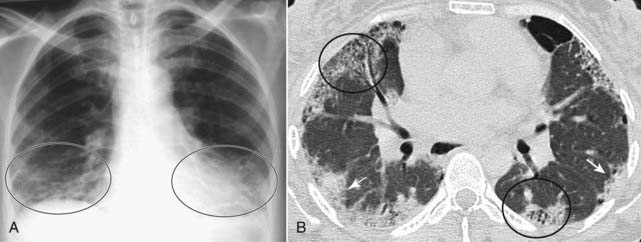

Figure 3-4 Silhouette sign, right middle lobe pneumonia.

A, Fluffy, indistinctly marginated airspace disease is seen to the right of the heart. It obscures the right heart border (solid black arrow) but not the right hemidiaphragm (dotted black arrow). This is called the silhouette sign and establishes that the disease (1) is in contact with the right heart border (which lies anteriorly in the chest) and (2) is the same radiographic density as the heart (fluid or soft tissue). Pneumonia fills the airspaces with an inflammatory exudate of fluid density. B, The area of the consolidation is indeed anterior, located in the right middle lobe, which is bound by the major fissure below (dotted white arrow) and the minor fissure above (solid white arrow).